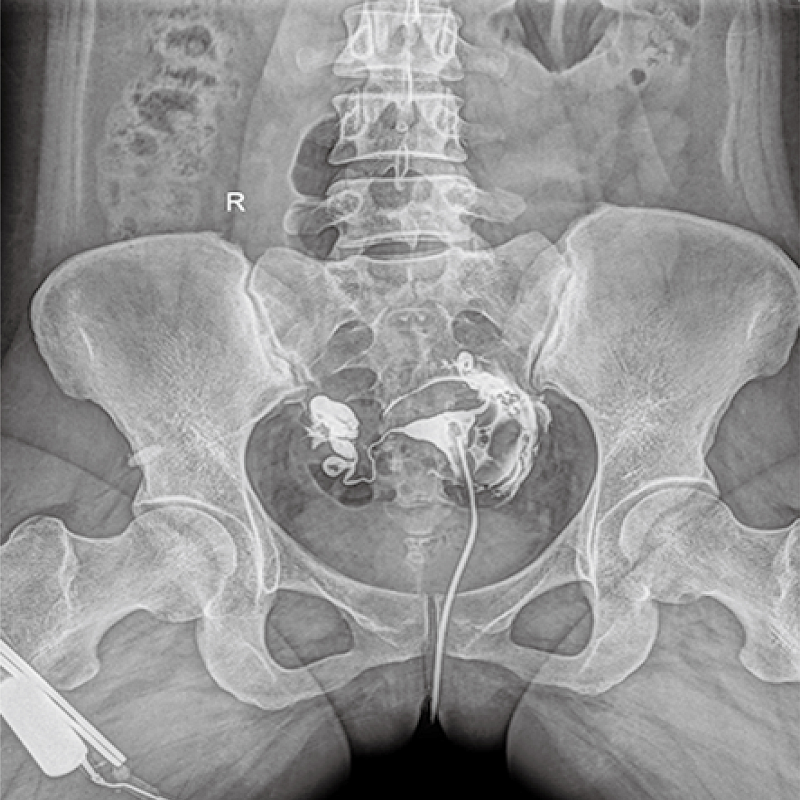

多功能、全視角、真視界,全面突破傳統X線(xiàn)攝影透視理念,通過(guò)一塊新型動(dòng)態(tài)平板探測器,在檢查中既可實(shí)現數字透視又可實(shí)現數字攝影,還可做數字胃腸及數字造影檢查。

● 只需一塊動(dòng)態(tài)平板探測器,高效輕松實(shí)現攝影、透視和造影功能,幾乎可以滿(mǎn)足醫院全科室

●呈現全下肢或全脊柱圖像

●在脊柱及下肢畸形矯正手術(shù)治療中,為術(shù)前方案制定和術(shù)后復查提供精準測量

●有效解決傳統X光片不能一次成像問(wèn)題,為患者提供更加優(yōu)質(zhì)的醫療服務(wù)

點(diǎn)片裝置可實(shí)現大范圍縱向移動(dòng),高效完成各部位、全身拼接等檢查需求